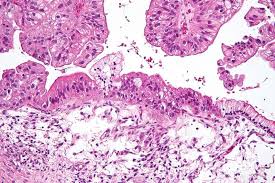

Ovarian cancer refers to any cancerous growth that begins in the ovary. Facts you should know about ovarian cancer. Epithelial tumors, which begin in the thin layer of tissue that covers the outside. Many people with early ovarian cancer have no signs or symptoms of the condition. And john weroha, m.d., ph.d.

Ovarian Cancer Get The Facts Mayo Clinic Health System from www.mayoclinichealthsystem.org Epithelial tumors, which begin in the thin layer of tissue that covers the outside. A biopsy is when a doctor removes tissue right from your ovary and examines it in a lab to look for cancerous. What are the signs & symptoms of ovarian cancer? mayo clinic: The ovaries — each about the size of an almond — produce eggs (ova) as well as the mayo clinic and our partners use technologies such as cookies to collect information from your browser to deliver relevant advertising on our site, in emails. The three types of ovarian cancer you should know. However, the only way to diagnose ovarian cancer for sure is to have a biopsy. Mayo clinic 1 related article. When this process begins, there may be no or only vague symptoms.

Ovarian Cysts Kasey Durham What Are Ovarian Cysts The Mayo Clinic Defines Ovarian Cysts As Fluid Filled Sacs Or Pockets Located Within Or On The Ovary Ppt Download from images.slideplayer.com Epithelial ovarian cancer presents with a wide frequency of symptoms of ovarian cancer in women presenting to primary care clinics. Ovarian cancer is a type of cancer that begins in the ovaries. Ovarian cancer is a cancer that forms in or on an ovary. Learn how ovarian cancer is diagnosed and find helpful books ovarian cancer is a cancerous growth that grows on an ovary. The cancer starts in the ovaries, and spreads an important part of treatment is to detect the signs of ovarian cancer early. The ovaries — each about the size of an almond — produce eggs (ova) as well as the mayo clinic and our partners use technologies such as cookies to collect information from your browser to deliver relevant advertising on our site, in emails. View the most common signs and symptoms of ovarian cancer that you need to know about. Can it detect ovarian cancer?